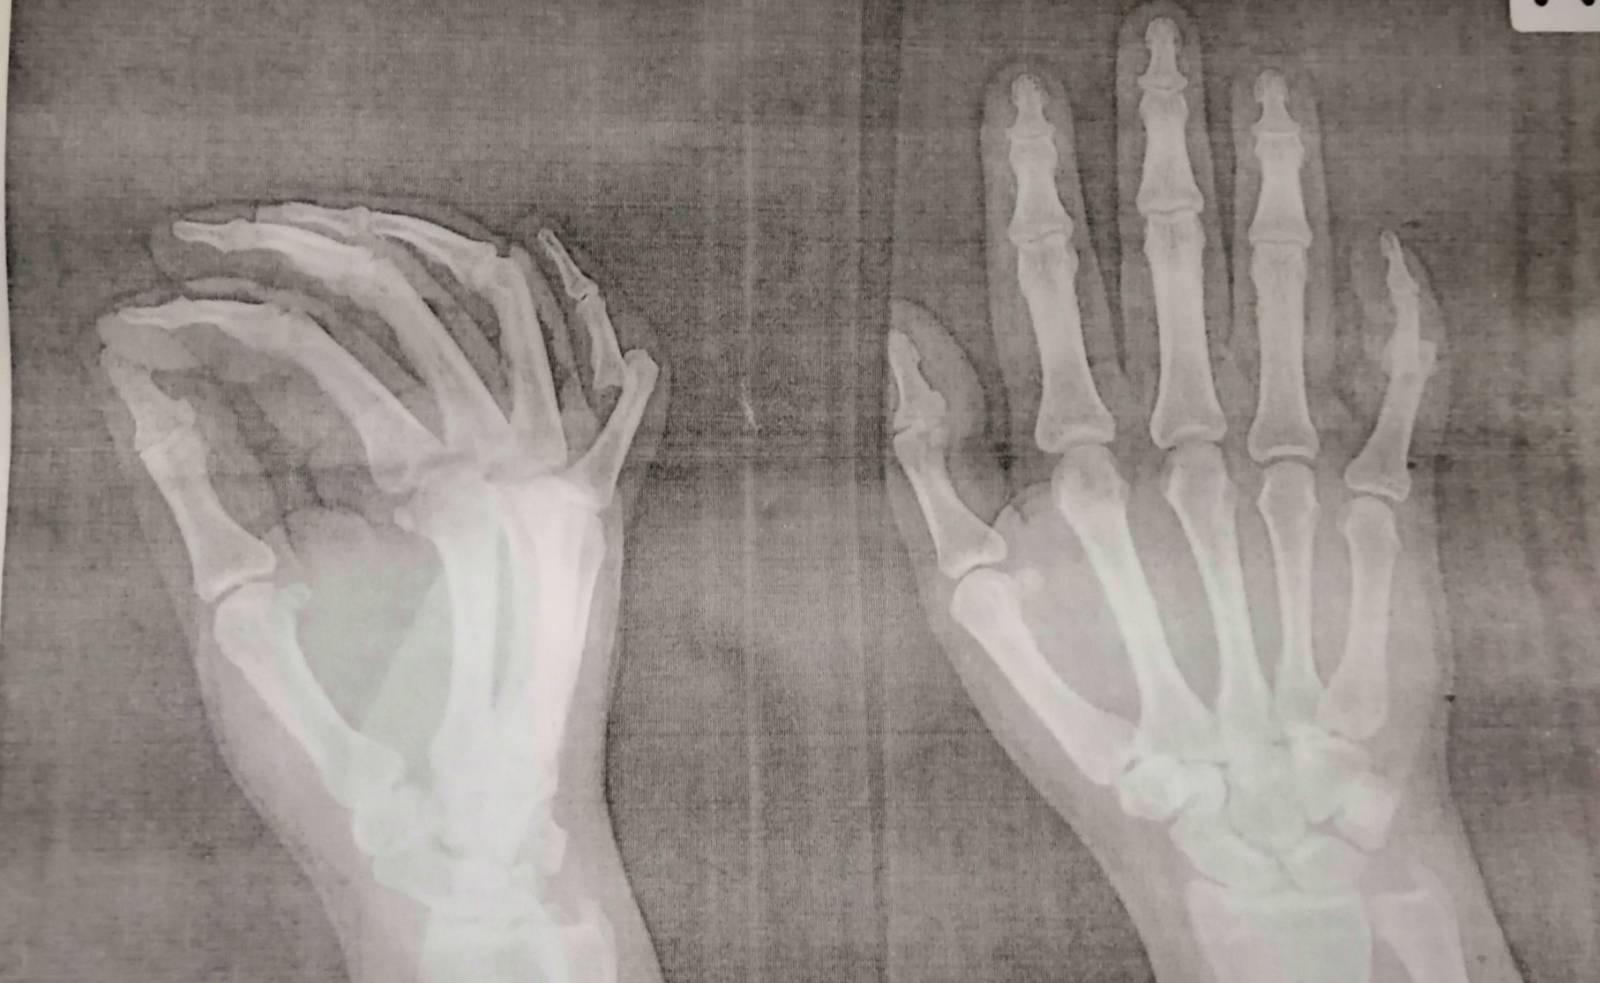

นิ้วก้อยข้อที่ 2 เคลื่อน

นิ้วก้อยมือข้างขวาข้อที่ 2 กระดูกเคลื่อนหมอดึงเข้าและให้ดามไว้ 1 เดือน พอเอาที่ดามออกนิ้วมันเหยียดตรงไม่ได้เลยค่ะ จะงอเข้าพยายามเอามืออีกข้างช่วยดัดแต่ดัดไม่ได้ค่ะมันเจ็บ และหมอที่ รพ. ไม่ได้นัดแล้ว ใครพอจะมีวิธีทำให้ตรงได้มั้ยคะ กลุ้มใจมากเลยค่ะ